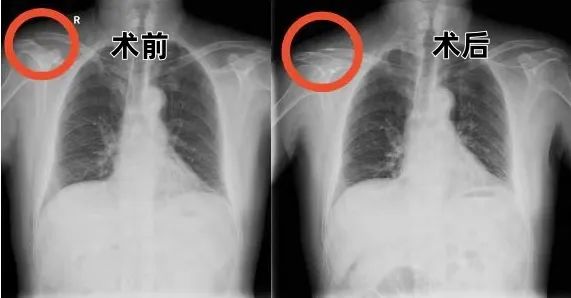

丁先生的病情到底是什么情况呢?骨科(关节、创伤,运医)中心主任甘煜东教授指着X线影像解释道:“患者的肩锁关节完全脱位,合并喙锁韧带断裂,属于RockwoodⅢ型损伤,这类损伤保守治疗容易遗留肩关节不稳、慢性疼痛等问题。传统手术创伤大、易残留肩部畸形,所以我们决定采用关节镜下袢钢板固定——就像用特制缆绳把脱位的关节精准锚定,这项技术对解剖重建的要求极高,但能最大限度保留肩关节功能。”

经过完备的术前检查后,甘煜东专家团队很快就为丁先生实施了“肩关节镜下肩锁关节脱位修复术”。

通过3个5毫米-10毫米的微小切口,在高清关节镜视野下,采用可调节带袢钛板模拟喙锁韧带生物力学轨迹,完成了解剖级精准重建。手术历时40分钟,出血仅5毫升。